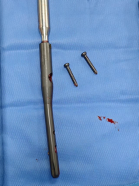

手术台上,团队创新采用"双重修复"策略——

精准清障

先小心翼翼取出嵌在盆腔的钢钉,避免损伤血管;

稳固支撑

植入特制加长股骨柄假体,像"钢筋"一样牢牢固定新关节。